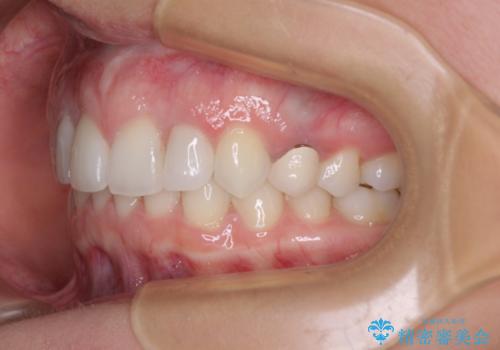

- 前歯の歯並びと神経を取って変色してしまった前歯を気にして来院された患者様です。

上下前歯の歯列不正はインビザラインにより整え、その後に、前歯2本をオールセラミッククラウンにて補綴治療することとしました。

下顎前歯が1本欠損しており、下顎歯列の大きさが本来よりも小さいため、上顎歯列とのバランスが悪く、深い咬み合わせになっていました。

上顎にIPRを多用して歯列の大きさを小さくするよう試みましたが、理想的な咬み合わせまでには改善させることはできませんでした。